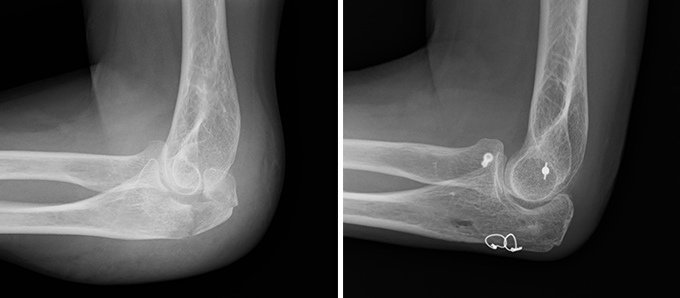

肘関節脱臼

転倒やスポーツ中の転倒で手をついたときなどに、肘の骨同士が外れてしまう外傷です。最も多いのは後方脱臼で、激しい痛みと腫れ、変形を伴い、肘を動かすことができなくなります。治療はまず整復(脱臼を戻すこと)を行い、骨折や靭帯損傷の有無をCTやMRIで精査します。関節が安定していれば一時的な固定後に可動域訓練を始め、靭帯損傷が強い場合は手術で修復します。早期に適切な治療を行うことで後遺障害を最小限に抑えることができます。

症例 10代後半 女性(保存加療)

(受傷時)

(受傷後 16か月)